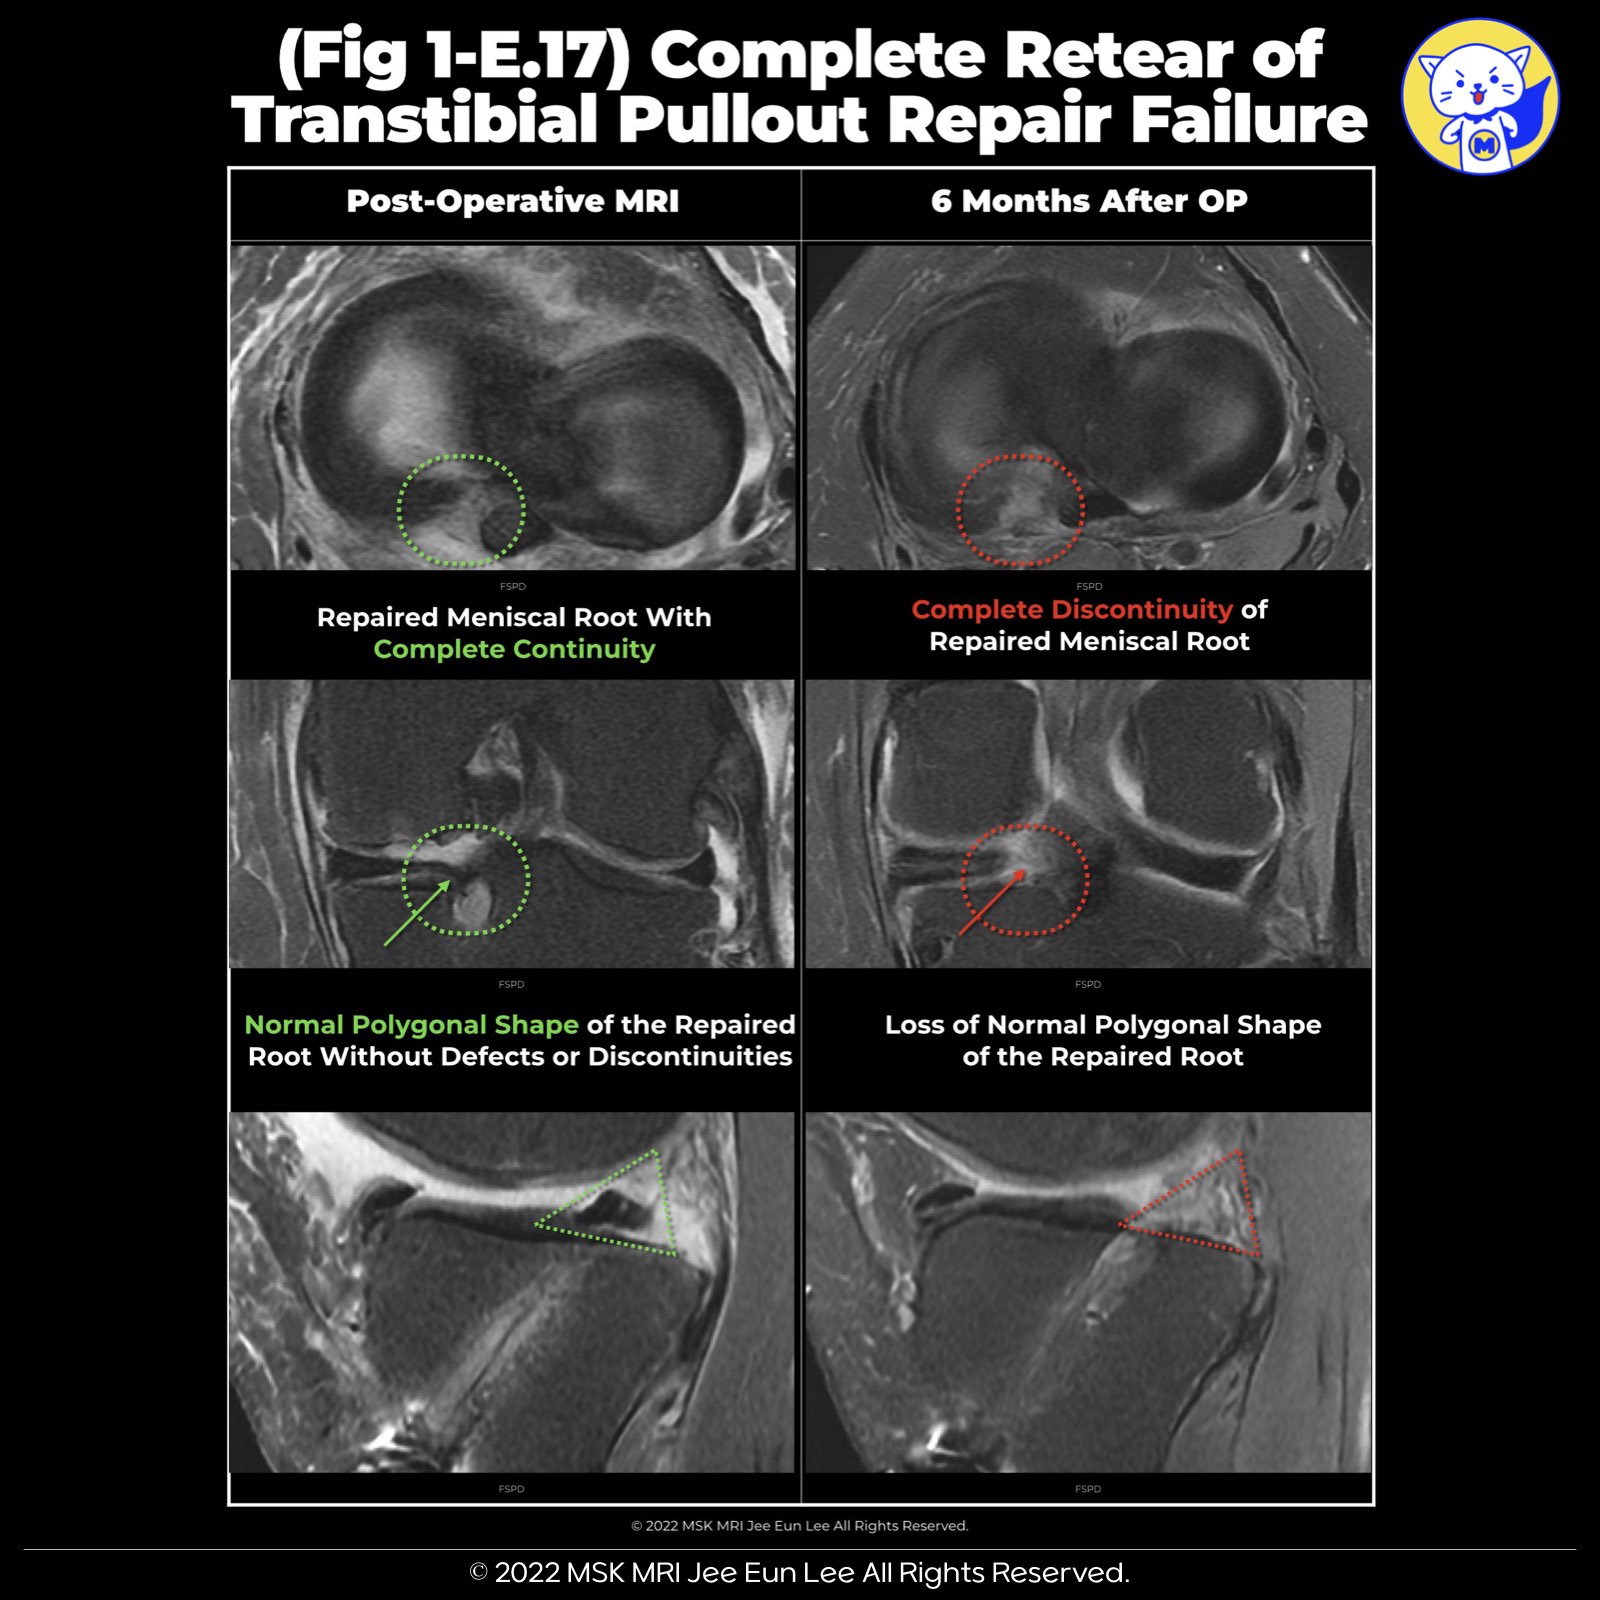

✅Summary of Meniscal Root Repair Healing Criteria and MRI Interpretation Challenges

• Complete Healing: Defined as the continuity of the repaired meniscal root across axial, coronal, and sagittal planes.

• Partial Healing: Identified when continuity is observed in one or two of these planes.

• Repeat Tear: Recognized by the absence of continuity in all three planes.